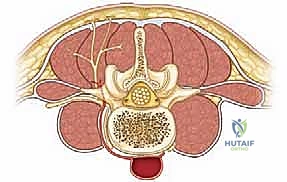

FIG 1 • Anterior view showing position of S-rod or S-hook with reference to L5 nerve root. Notice how the released ileotransverse ligament provides unhindered access.

The L5 Nerve Root

This is our most significant neurovascular concern in this region. The L5 nerve root traverses anterior to the sacral ala. Its trajectory is oblique, progressing from posterior to anterior and superior to inferior, originating from the neural foramen of L5. Crucially, immediately inferior to the L5 pedicle, the nerve passes anterior to the sacral ala, separated by a distance of approximately 1.5 cm. This means any instrument blindly inserted anterior to the ala is at high risk of injuring this root.

Retroperitoneal Space

Immediately anterior to the sacral ala, beyond the L5 nerve root, lies the retroperitoneal fat. Plunging an instrument too far anteriorly risks entering this space, with potential for injury to major vessels (iliac vessels), ureters, or bowel.